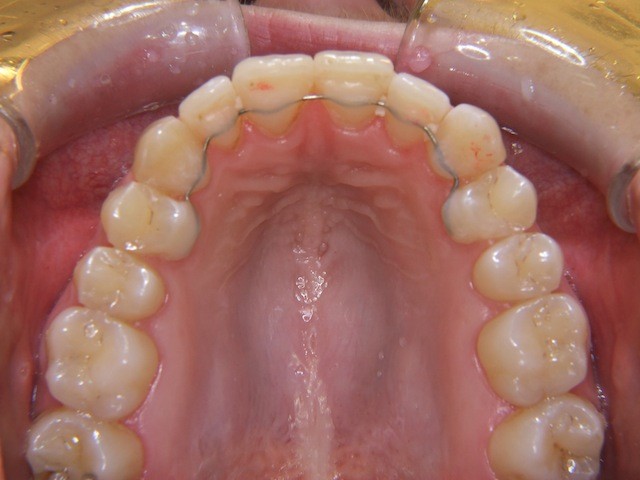

Beispiel einer Engstandsbehandlung bei einem Erwachsenen mit Invisalign

Vorher ----------------------------------- Nachher

Bilderserie Invisalignbehandlung Oberkiefer mit Stabilisierungsdraht am Schluss. Man beachte die Ansammlung von Belägen und Verfärbungen infolge Nischenbildung am Zahn der am meisten im Engstand steht.